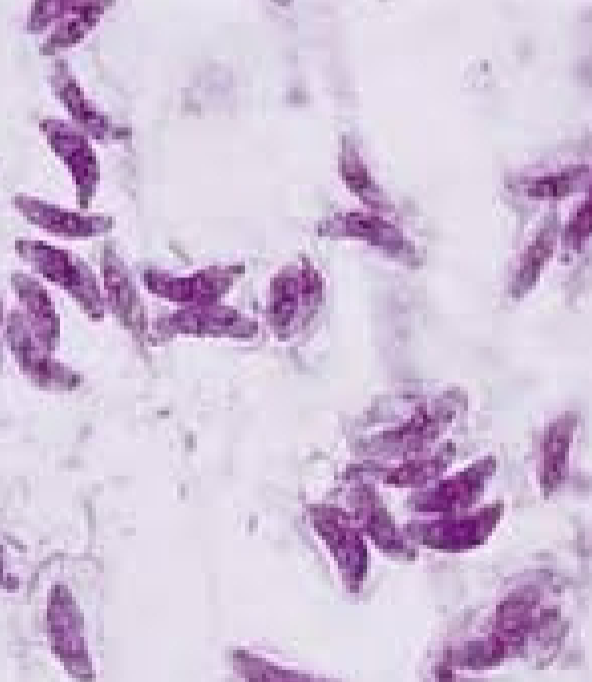

Toxoplasma gondii Tachyzoites